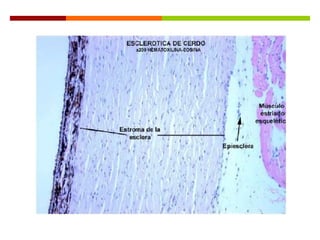

 La esclerótica está formada por 3 capas:

 Fusca: es la capa más interna y contiene abundantes